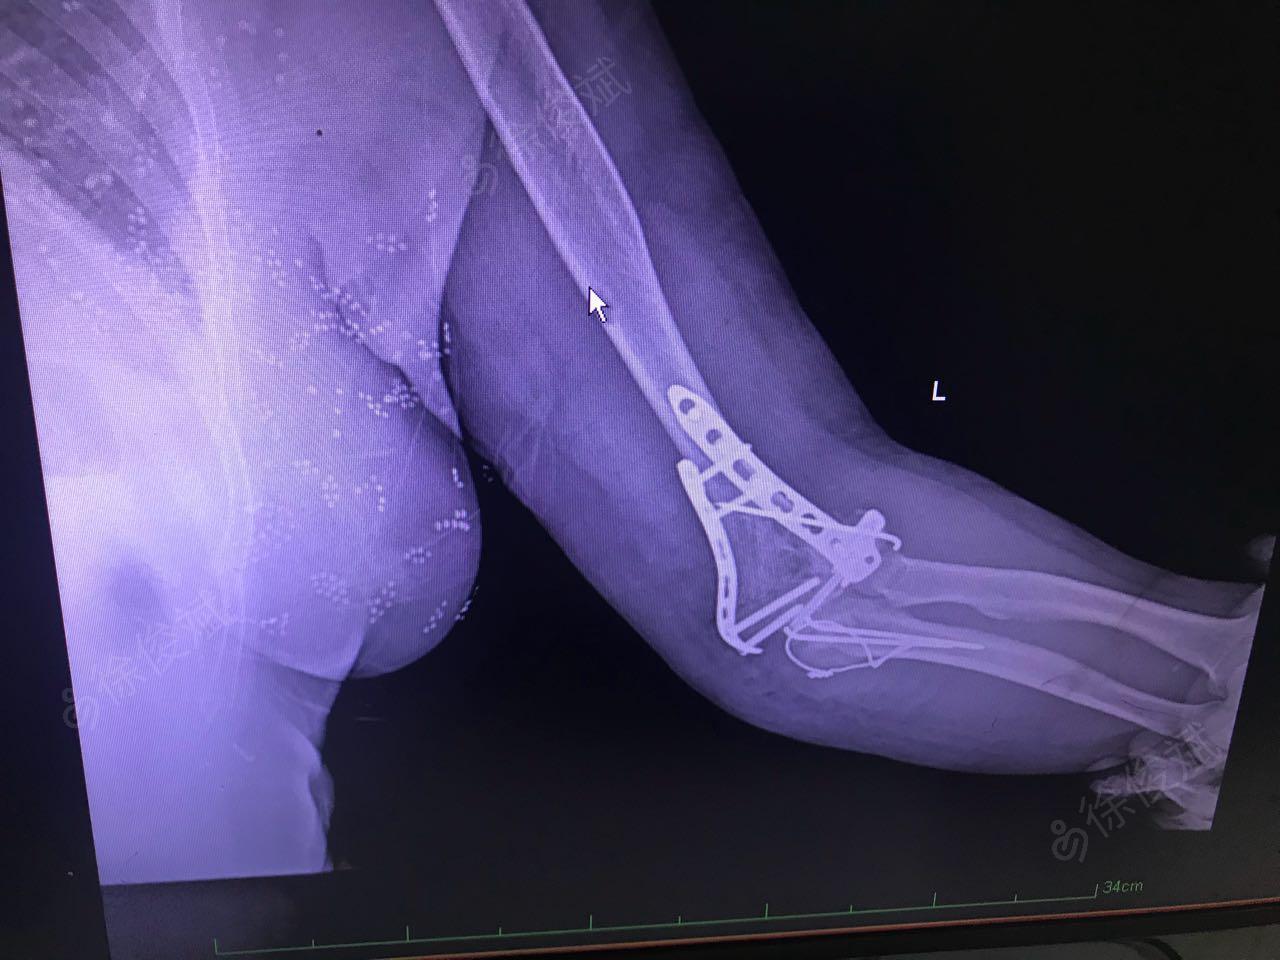

左侧肱骨外髁骨折

图片尺寸1862x2101